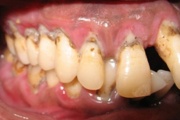

Agressiivne parodontiit

Seda parodontiidi vormi esineb umbes1%-l elanikkonnast. On haiguse kiiresti progresseeruv vorm, mille puhul patsiendid kaotavad kõik hambad enne30-35. eluaastat. Tavaliselt haigestutakse piimahammaste lõikumise ja puberteedi vahele jääval perioodil. Jagunemine:- lokaliseeritud agressiivne vorm- Loe edasi »